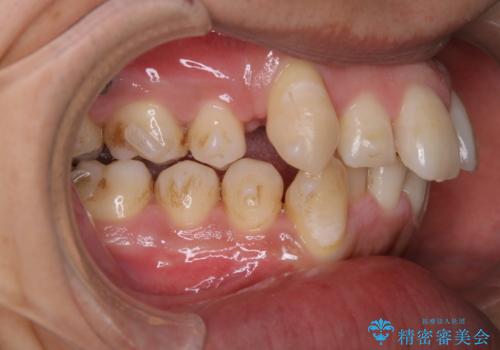

- インビザラインでの矯正治療中に、アタッチメント周囲のステインが気になるとのことでした。PMTC30分コースで、特に見える表側のステイン除去を行いました。

マウスピース矯正インビザライン治療では、歯の表面にアタッチメントという突起を設定します。(アタッチメントは歯の動きを効率的に移動するためのものです)

アタッチメントが歯に付くと、表面が凸凹し磨き残しが多くなったりと、プラークや歯石・着色がつきやすくなることがあります。